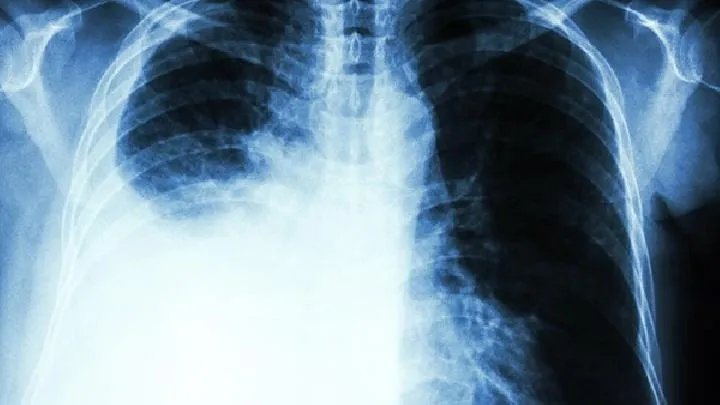

间质性肺炎后期治疗

的有关信息介绍如下:间质性肺炎是指终末气道,肺泡和肺间质的炎症,可由疾病微生物、理化因素,免疫损伤、过敏及药物所致,细菌性肺炎是最常见的肺炎,也是最常见的感染性疾病之一,那么,间质性肺炎后期治疗方法有哪些呢?